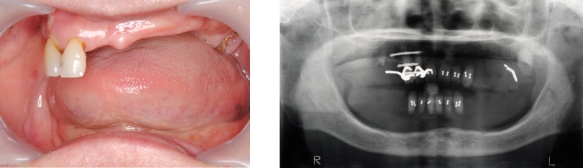

インプラント症例③ ~ほとんど歯が無い例~

●残っている歯が2本しかなく、上下、入れ歯を何度と作っているが、全然合わない。

●上にはインプラントを6本入れて、固定式の歯を入れました。

●下にはインプラントを4本入れて、マグネットを取り付けて、安定する入れ歯にしました。